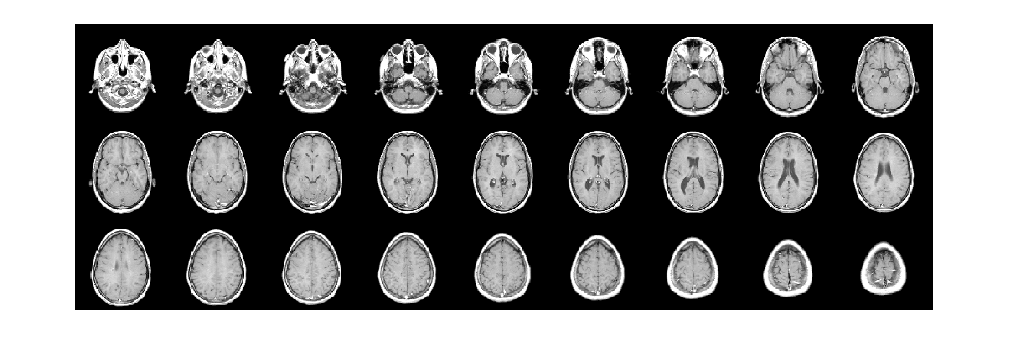

Загрузите 3-D объемный набор данных в рабочую область.

s = load(fullfile(toolboxdir('images'),'imdata','BrainMRILabeled','images','vol_001.mat')); V = s.vol;

Отобразите горизонтальные срезы данных при помощи montage функция.

montage(V,'Indices',12:118,'Size',[8 12],'DisplayRange',[]);